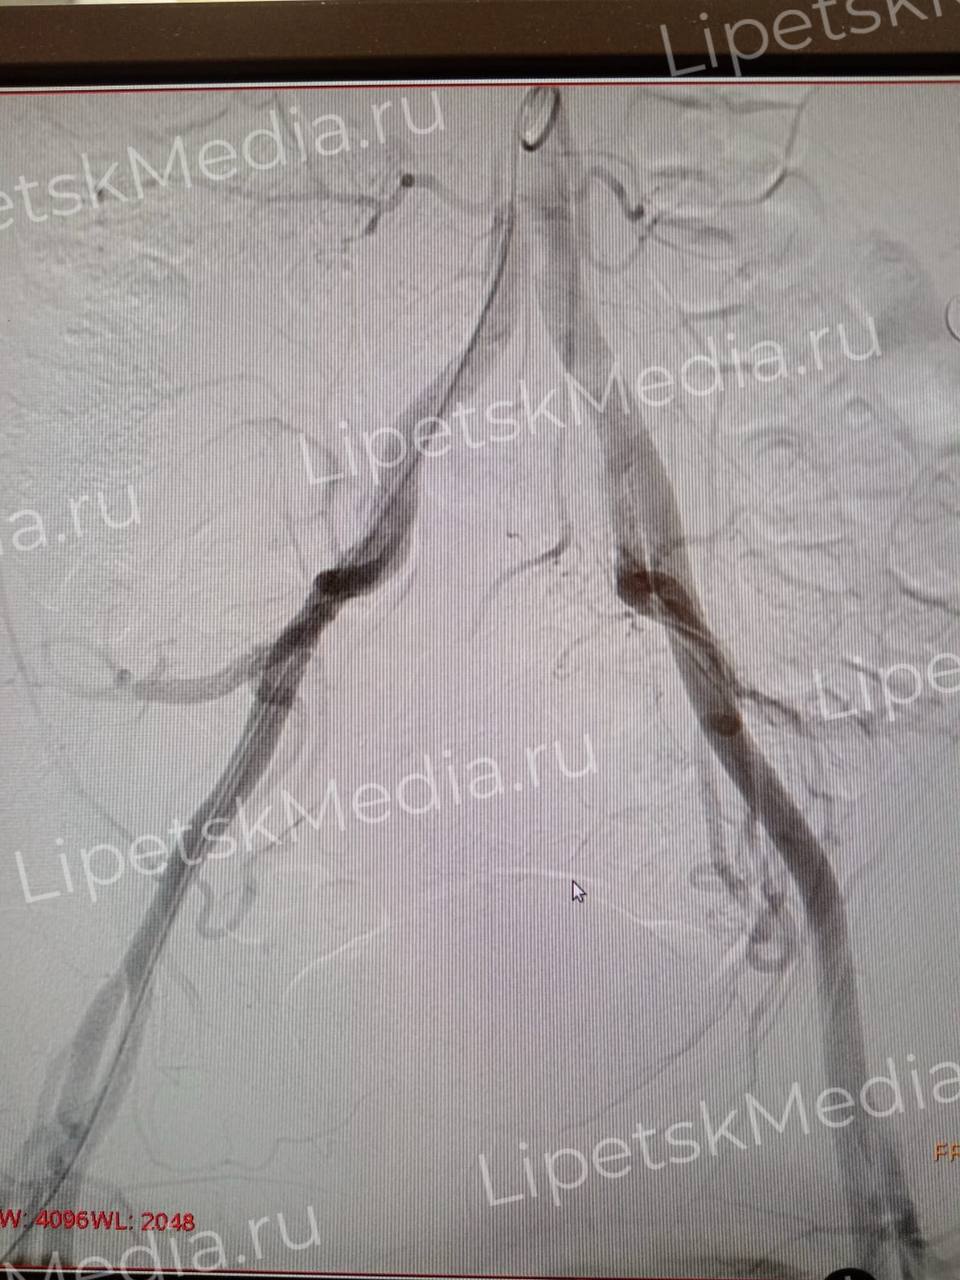

После тщательного обследования им выполнили эндоваскулярные операции по эмболизации маточных артерий.

Во время вмешательства в кровоснабжающие сосуды миомы матки вводят эмбосферы. Они перекрывают просвет сосуда, опухоль перестает расти, а в дальнейшем уменьшается в размерах, сообщают медики.